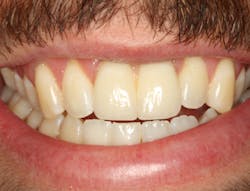

The same arguments have been advanced for not splinting adjacent implants in segmental reconstructions (figure 1). Plaque-related peri-implantitis is the most common biological complication in implant dentistry. A passive fit of prostheses on their supporting implants is considered essential for minimizing mechanical and biological overloading. On the other hand, it is also claimed that splinting can prevent overloading (figure 2). Screw loosening and fracture of veneering material are the most common mechanical complications of loading, although there is little evidence that it results in loss of integration.

Figure 2: Splinted adjacent implants